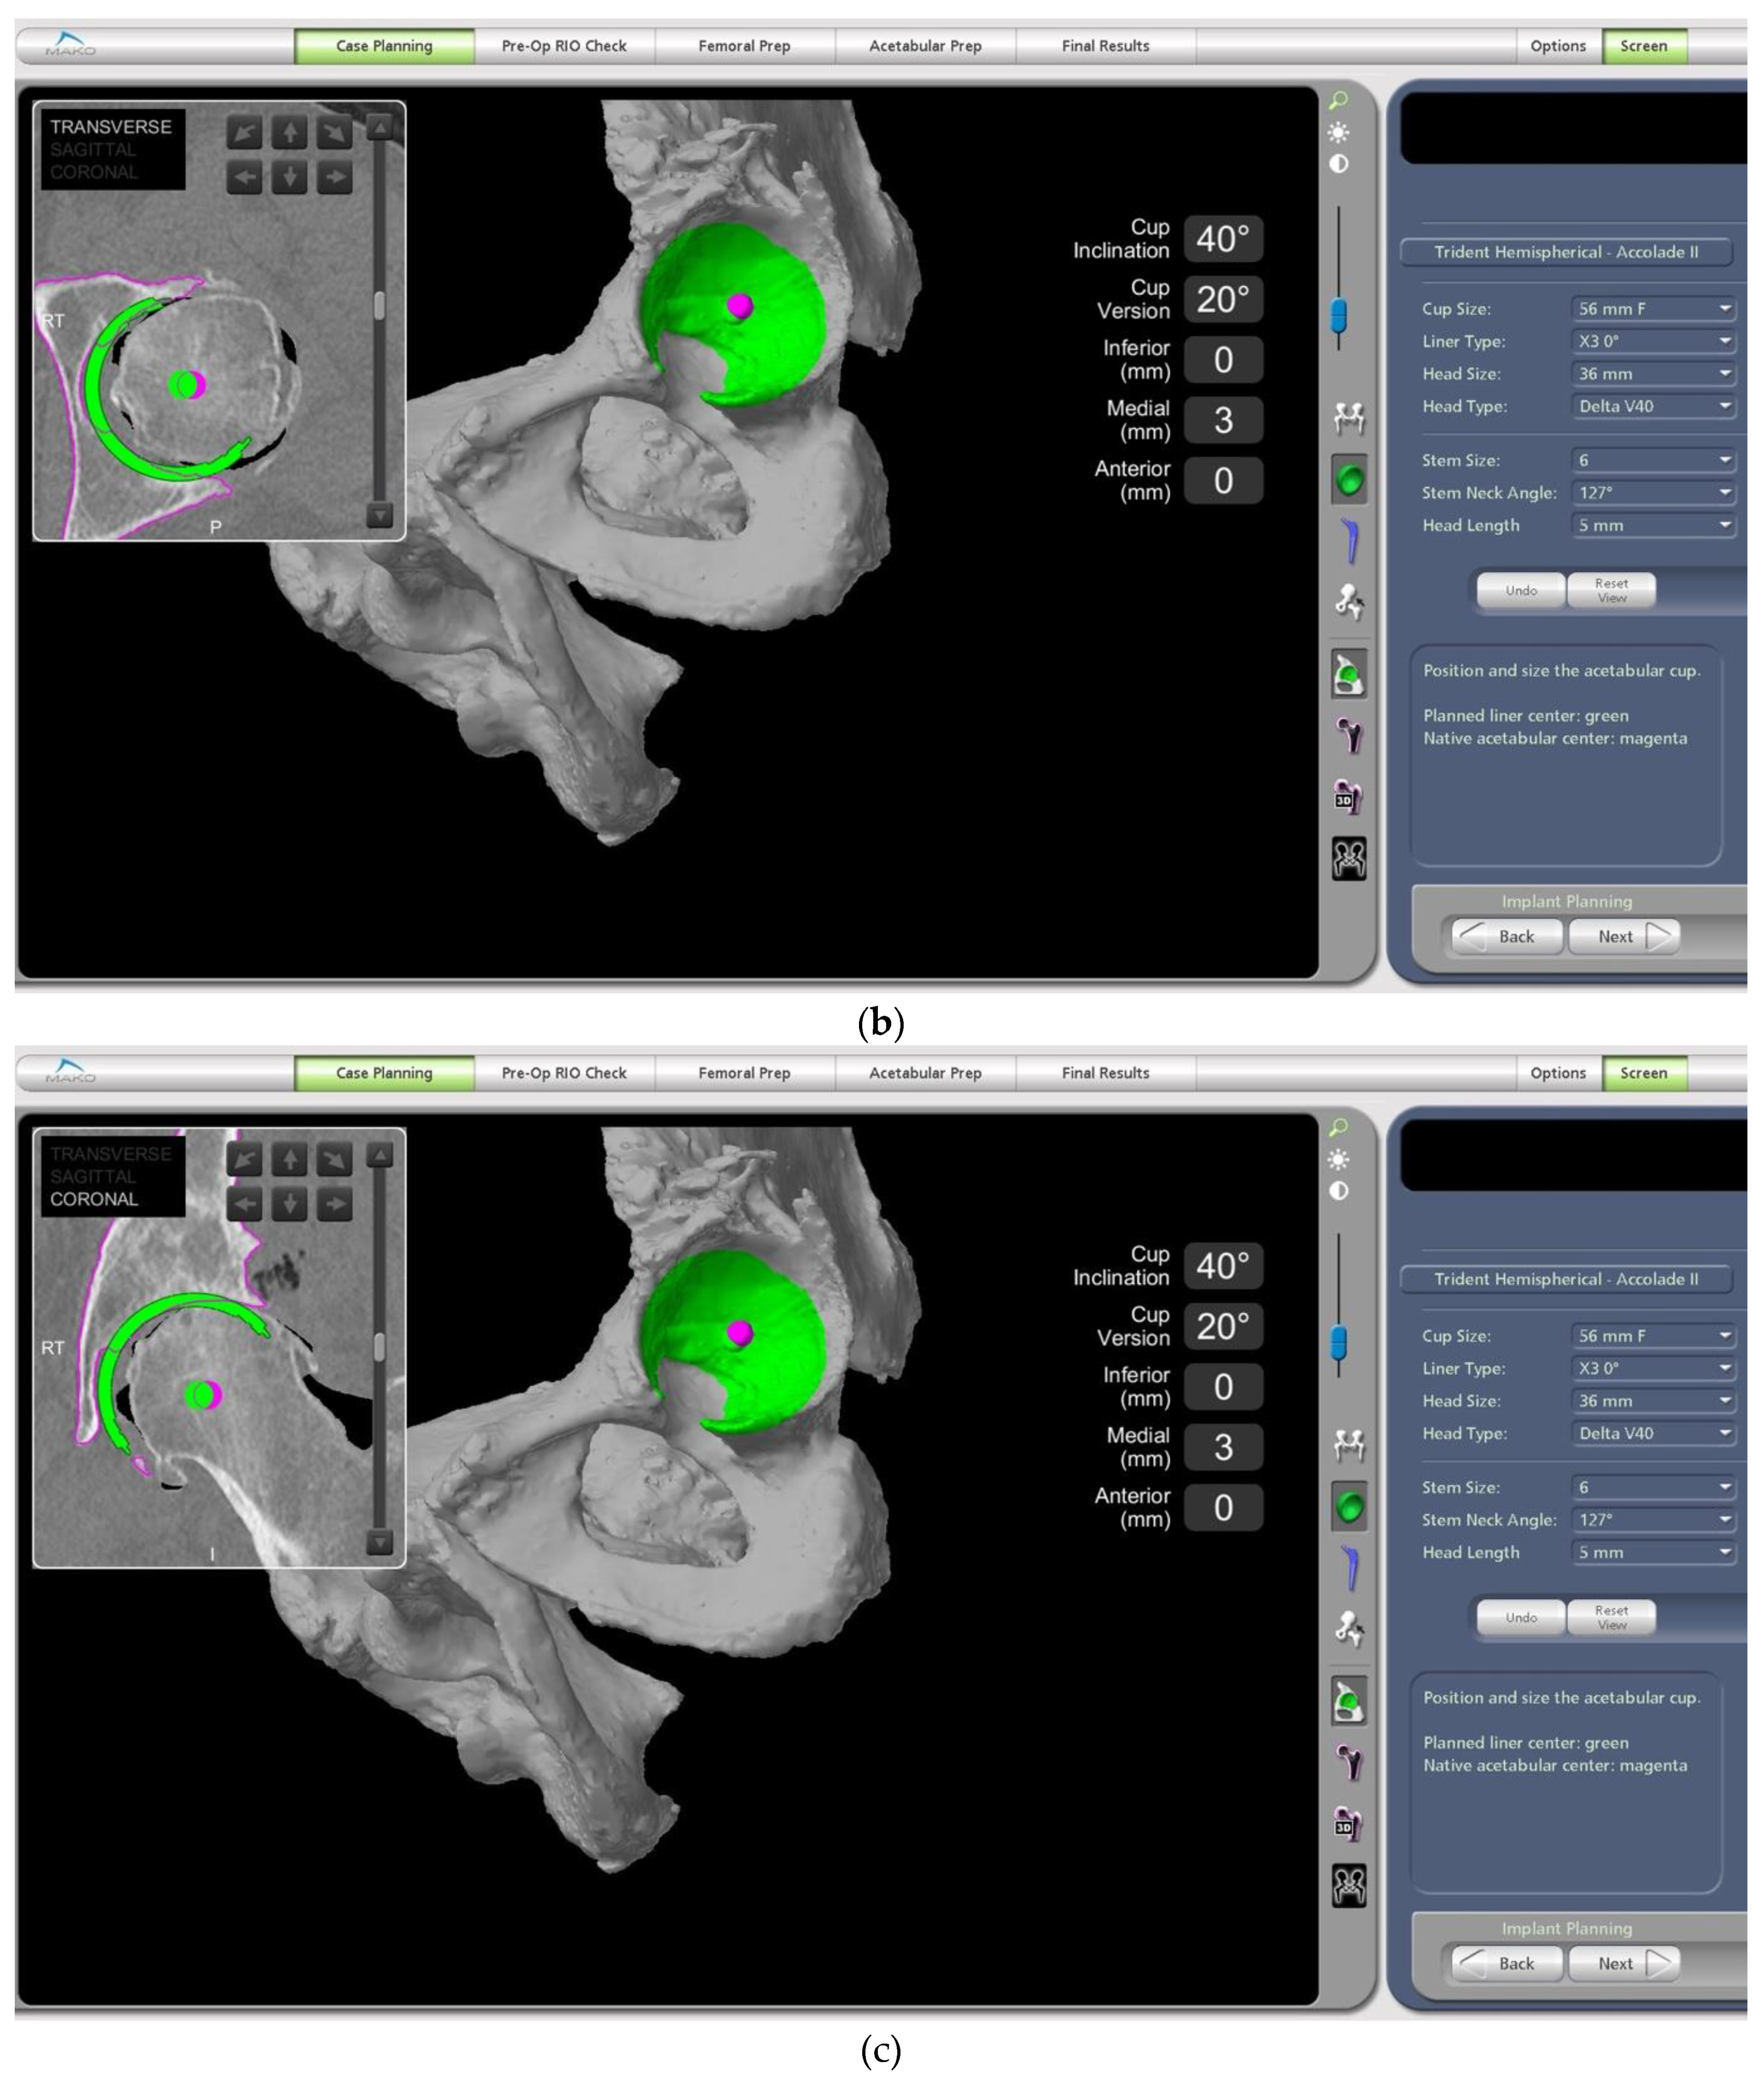

- In this case, the native femoral retroversion (−6 degrees) posed a challenge in avoiding impingement (Figure 7). Upon assessing VROM, bone-on-bone and implant-on-implant impingement in deep flexion were noted (Figure 8). Using the robotic software, the planned femoral version was corrected to +16 in the femoral broach (Figure 9a,b).

- The robotic software also enables preoperative and intraoperative visualisation of the anticipated postoperative X-rays accounting for any changes to the plan. In addition, the software allows for calculation of changes to the leg length offset compared to the preoperative and contralateral hips. In this case, the leg length was 1 mm longer compared to the opposite hip, and the combined offset was 6 mm increased compared to that preoperatively (Figure 12a,b).